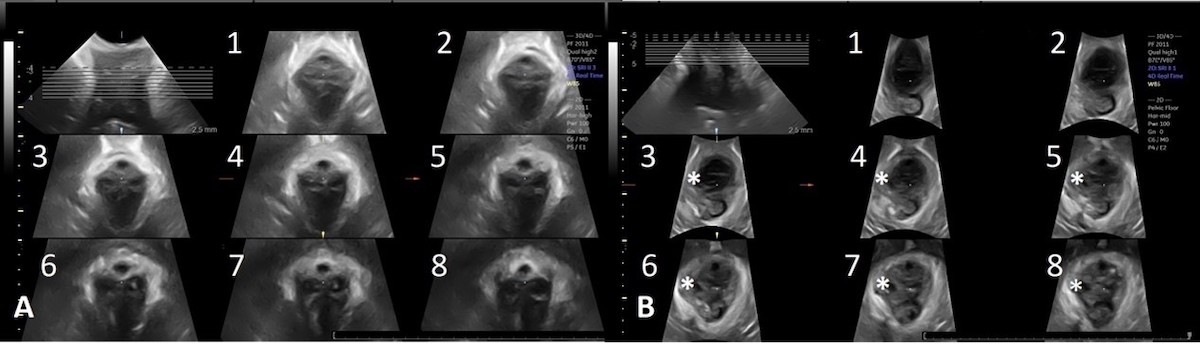

POP can be considered a hernia, with the levator hiatus the hernial portal. Both integrity of the levator ani and the size of the levator hiatus are important in the pathophysiology of POP and are predictors of prolapse recurrence (Handa et al 2019; Friedman et al 2018). Pelvic floor imaging should be part of POP assessment to facilitate patient counseling, surgical planning and in treatment audit. 3D/4D translabial ultrasound allows a direct and reproducible assessment of the levator ani and hiatus. It also facilitates training of the clinical assessment of levator ani by providing immediate visual biofeedback to the examiner (Figure 2).

Figure 2: Tomographic ultrasound imaging of an intact levator (A) and right sided levator avulsion (B). The right sided defect is marked by * in slices 3-8 in Image B.